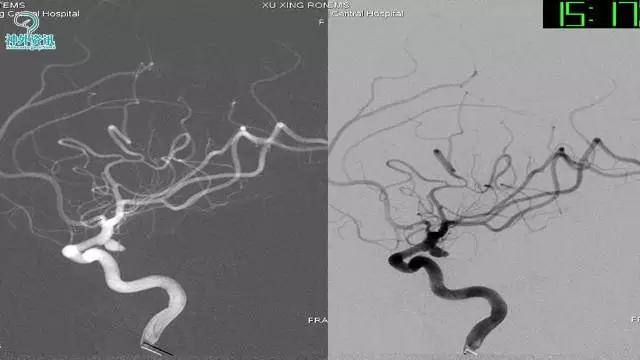

今天为大家分享的是“强生医疗CNV-神经介入专栏”第三十六期,由重庆第三军医大学附属新桥医院神经外科刘俊带来的“Galaxy弹簧圈在不规则动脉瘤中的临床应用”精彩讲课视频及PPT,欢迎观看。文章仅代表作者个人观点,如有不同见解,欢迎同道斧正!